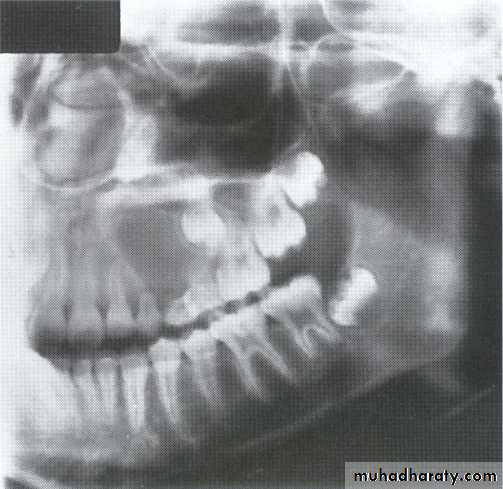

• Aneurysmal Bone Cyst

•Large multilocular aneurysmal bone cyst

in the ramus with marked expansion and

the displacement of/8.

It is non-neoplastic ,exaggerated,localized, proliferative lesion of vascular tissue, containing giant cells.

It’s a variation of the central giant cell granuloma , can be diagnosed only by histological examination